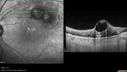

Self Sealed Retinal Arteriol Macroaneurysm - one month after presentation - edema nearly gone504 viewsSD OCT line scan

Self Sealed Retinal Arteriol Macroaneurysm - MAP shows decreased swelling500 viewsSD OCT map

Self Sealed Retinal Arteriol Macroaneurysm- one month after presentation - edema nearly gone430 viewsSD OCT line scan